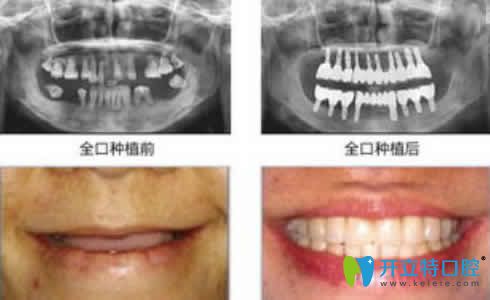

湛江致美口腔李啟森主任全口種植牙案例效果賞析: